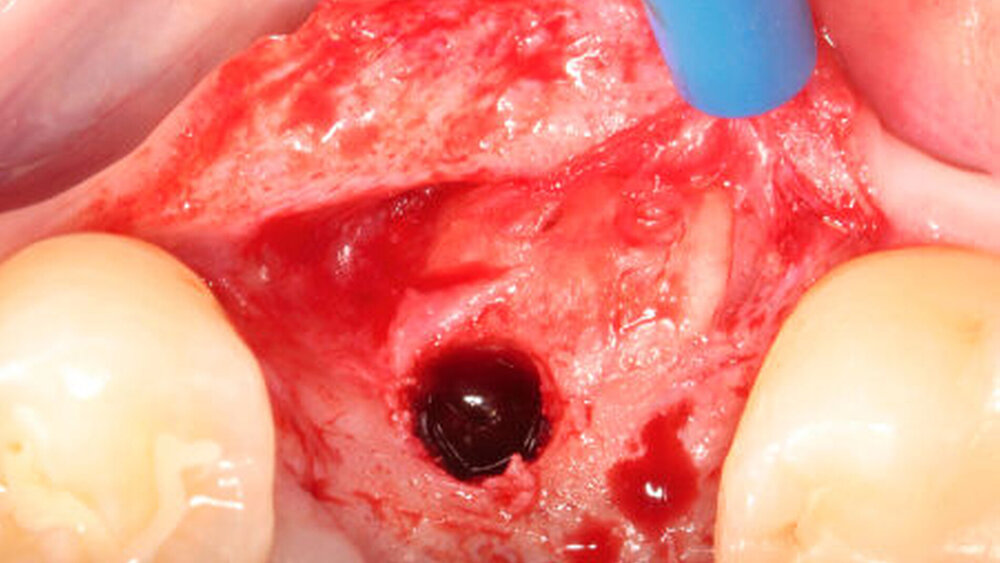

Nach einer plastischen Deckung des Wundgebiets zeigte die Wiedereröffnung nach einer Heilungsphase von zwölf Wochen in allen Gruppen eine vergleichbare homogene Integration der jeweiligen Augmentate im ehemaligen Defektbereich (Abbildung 2b).

In den oben genannten tierexperimentellen Untersuchungen zur lateralen Augmentation chronischer Kieferkammdefekte unter Verwendung von Zahnwurzelaugmentaten wurde zudem die frühe Einheilphase enossaler Titanimplantate im Defektbereich bewertet [Schwarz et al., 2016c; Schwarz et al., 2016a]: Nach einer Heilungsphase von drei Wochen war die histomorphometrisch bewertete frühe Osseo-, beziehungsweise Dentointegration der eingebrachten Titanimplantate im Bereich der Zahnwurzelaugmentate (Mediane: 36,96 bis 50,79 Prozent) mit der im Bereich der autogenen Knochenblöcke (Mediane: 32,53 bis 64,10 Prozent) vergleichbar (Abbildung 4). Die gemessenen Werte sind mit den frühen – das heißt nach zwei Wochen – prozentualen Knochen-Implantat-Kontakten von 58,8 Prozent bis 59,3 Prozent im nativen Knochenlager grundsätzlich vergleichbar [Schwarz et al., 2007a; Schwarz et al., 2007b].